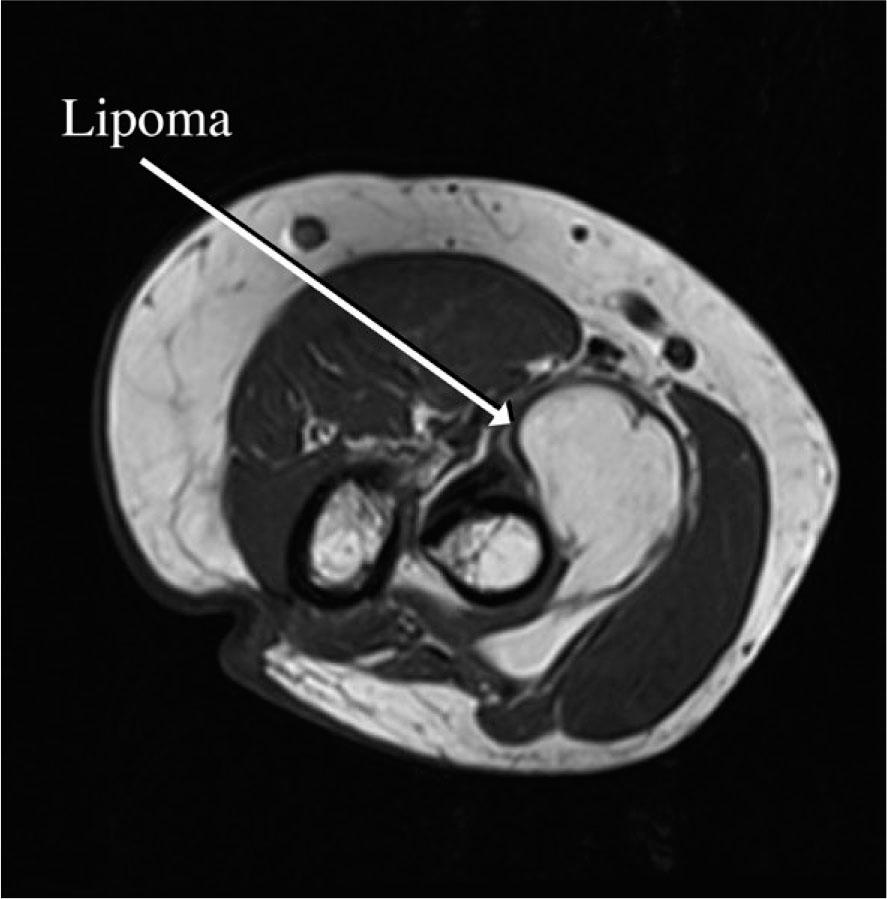

FIGURE 2.